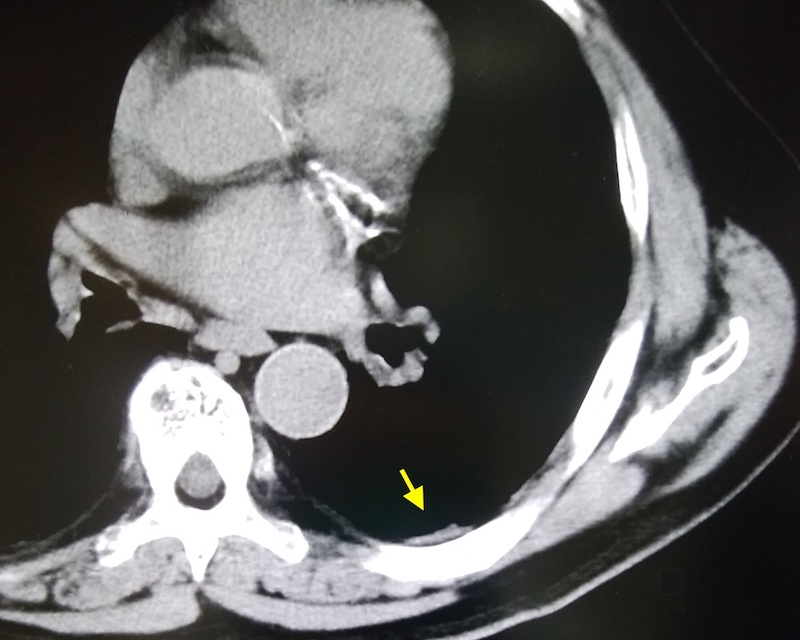

Bさんは、建設左官職で、アスベストはビル等で30年吸入しています。肺がんで死亡後、ご家族から相談がありました。わずかにCTで胸膜プラークを認めたので、名取が医師意見書を記載して遺族補償を労災保険に申請しました。数か月後に業務上として認定され、遺族補償をお受けになりました。

写真2 Bさん